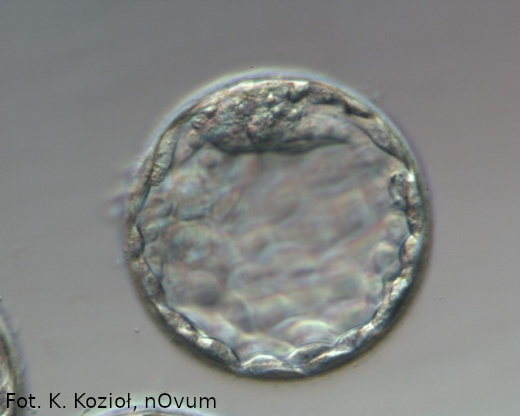

W piątym, a najdalej w szóstym dniu hodowli zarodek powinien osiągnąć stadium blastocysty. Na tym etapie część komórek grupuje się, tworząc wyraźny węzeł zarodkowy, z którego powstanie kiedyś dziecko, a część utworzy pojedynczą warstwę komórek na obwodzie zarodka (trofoektoderma), z której ukształtuje się łożysko. Cały zarodek znacznie się powiększa, a między węzłem zarodkowym a trofektodermą pojawia się płyn. Otoczka przejrzysta staje się bardzo cienka, a pod koniec piątego dnia rozwoju odcinkowo zanika i zarodek w stadium blastocysty zaczyna się z niej wydostawać, czyli „wykluwać się”. Jest to ostatni etap rozwoju, do którego zarodki są hodowane w laboratorium.

blastocysta 5 dni

Blastocysta, zarodek 5-o dniowy

W ciągu kolejnych 1–2 dni zarodki wyklują się z otaczającej błony i zaczną zagnieżdżać (implantować) w błonie śluzowej macicy.

blastocysta wykluwająca się

Blastocysta „wykluwająca się”